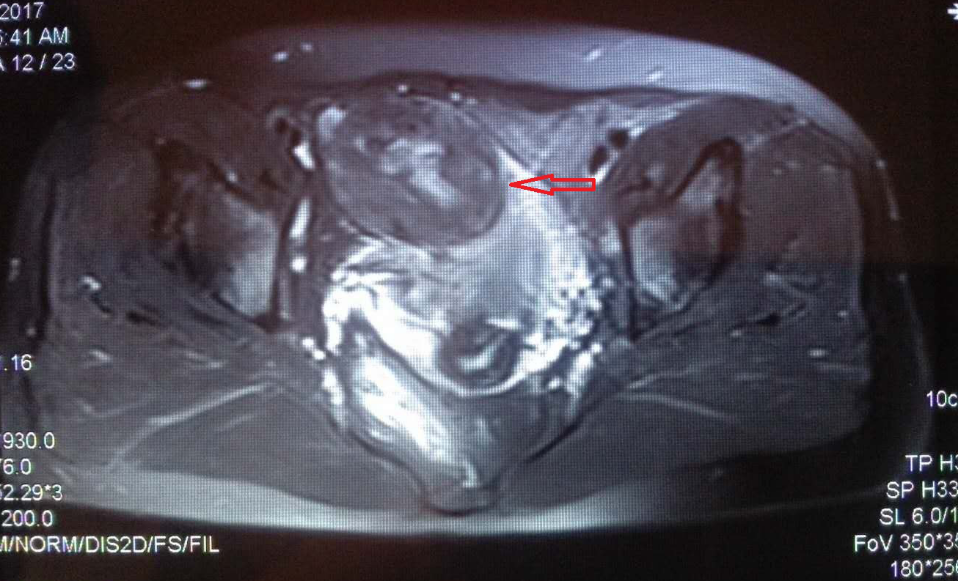

患者王女士(化名)患有子宫肌瘤2年多,由于已婚已育,并且发现是良性,便没有在意,谁知子宫肌瘤却在不断变大,并且每次月经很多,还伴有尿频的症状。为此,王女士颇为烦恼。遂就诊于北京燕化医院。经核磁检查,显示为子宫前壁巨大子宫肌瘤。

上图中,红色箭头所指为子宫前壁巨大子宫肌瘤,绿色箭头所指为子宫,黄色箭头所指为被子宫肌瘤压迫的膀胱。